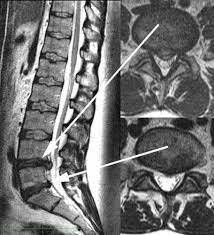

Bandscheiben op lws 4 5. Sie kommen meist zwischen den Wirbeln LWK Lendenwirbelkörper 45 und LWK 5SWK 1 Sakralwirbelkörper vor an der vorletzten und letzten Bandscheibe. Bandscheibenvorfälle sind Teil einer natürlichen Abnützung des Gewebes. Drückt der Gallertkern auf einen Rückenmarksnerven leiden Betroffene unter starken Rückenschmerzen die teilweise bis in Arme und Beine ausstrahlen.

Ursachen Diagnose und Therapie. Wie der Bandscheiben-Vorfall Prolaps ist die Bandscheiben-Vorwölbung Protrusion besonders häufig in der Etage bei L4L5 zwischen dem 4.

Wenn die Physiotherapie und Medikamente nicht mehr helfen und die Schmerzen zu stark sind oder wenn der Druck auf die Nerven Ausfälle verursacht Taubheit Muskelschwäche Lähmung sollte eine Operation in Betracht gezogen werden. Bandscheibenvorfall LWS Übungen - Hier findest du 5 effektive Übungen bei einem Bandscheibenvorfall in der Lendenwirbelsäule inkl. Es geht mir zur Zeit nicht gut mache mir auch große Sorgen wie es wird in den nächsten Tagen und Wochen mit den Schmerzen und Beschwerden. Ich wurde am 4. Frank aus München in. Probieren Sie es selbst aus. Sie kommen meist zwischen den Wirbeln LWK Lendenwirbelkörper 45 und LWK 5SWK 1 Sakralwirbelkörper vor an der vorletzten und letzten Bandscheibe. Die Bandscheiben der Wirbelsäule übt eine Art Stossdämpferfunktion aus und dient der Elastizität und der Beweglichkeit der Wirbelsäule. Lendenwirbel und dem 5.

Die Bandscheibenvorfälle an der Lendenwirbelsäule sind die häufigsten Bandscheibenvorfälle an der Wirbelsäule. In der Regel verschwinden die Schmerzen zwar nach der OP es kann aber immer sein dass sich Symptome nicht zurückbilden. Wenn die Physiotherapie und Medikamente nicht mehr helfen und die Schmerzen zu stark sind oder wenn der Druck auf die Nerven Ausfälle verursacht Taubheit Muskelschwäche Lähmung sollte eine Operation in Betracht gezogen werden. 3053 Beiträge ø047Tag Hallo vor 1 Woche hatte ich eine große Bandscheiben-OP. Wie der Bandscheiben-Vorfall Prolaps ist die Bandscheiben-Vorwölbung Protrusion besonders häufig in der Etage bei L4L5 zwischen dem 4. Bandscheibenvorfall 4-5 Lendenwirbel Hey S-A2011 danke für Deine Erzählung. Alleine in Deutschland werden jährlich ungefähr 150000 Bandscheibenvorfälle operativ behandelt.